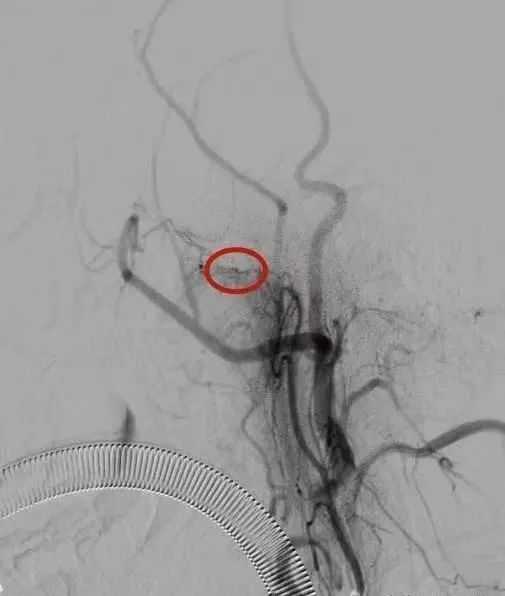

神经介入科副主任彭富考虑此次鼻出血因鼻咽癌侵犯动脉导致,建议立即行介入栓塞治疗。经过沟通,患者及其家属决定行介入栓塞治疗。随后,立即紧急启动绿色通道,送介入手术室急诊行介入手术止血。术中血管造影提示右侧颈外动脉咽外动脉分支可见活动性出血,由此“犯罪血管”被找到。通过直径头发丝大小的微导管送入“犯罪血管”进行生物胶精准栓塞,造影下见“犯罪血管”闭塞,出血停止。整个过程,只有股动脉的穿刺入路的穿刺口,创伤极少,恢复快,效果好。